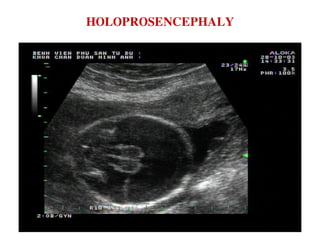

HOLOPROSENCEPHALY

NAÕO THAÁT DUY 1 + ÑOÀI THÒ BIEÁN DAÏNG

ÑOÀI THÒ BIEÁN DAÏNG